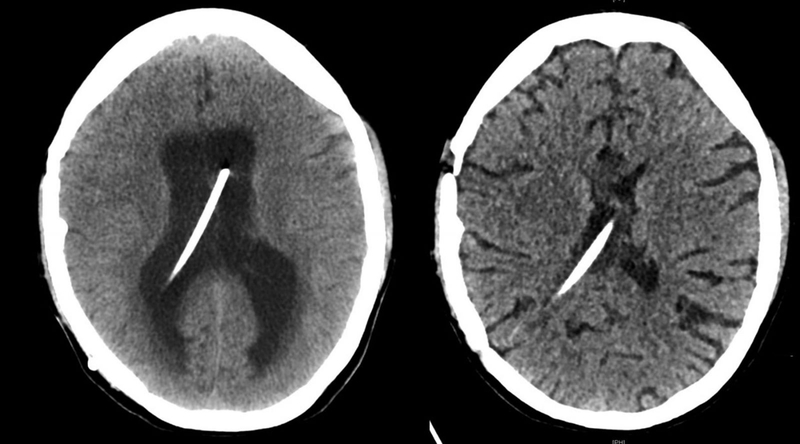

Não úng thủy là một tình trạng đặc trưng bởi sự tích tụ bất thường dịch não tủy trong não thất. Trong quá trình não úng thủy, chất lỏng dư thừa sẽ làm cho não thất giãn rộng. Biến chứng não úng thủy có thể sẽ xảy ra khi tình trạng này không được phát hiện và điều trị kịp thời, gây nguy hiểm cho tính mạng của người bệnh.

Não úng thủy là tình trạng xảy ra khi chất lỏng tích tự trong hộp sọ và gây phù não. Thông thường, dịch não tủy thường di chuyển trong các khoang của não, còn được gọi là não thất. Trong quá trình não úng thủy, chất lỏng dư thừa sẽ làm cho não thất giãn rộng, gây ảnh hưởng lên các bộ phận khác của não.

Tổn thương não có thể xảy ra do sự tích tụ dịch não tủy. Điều này có thể dẫn đến suy giảm khả năng phát triển về thể chất và trí tuệ. Tình trạng này cần được phát hiện và điều trị kịp thời để ngăn ngừa các biến chứng nghiêm trọng.